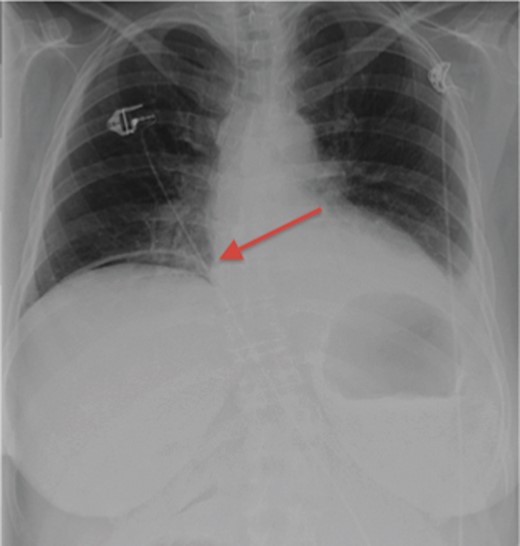

Her initial labs showed a normal WBC level of 8.3 thou/mcL; however, the patient was acidotic with a pH of 7.29 and a lactic acid level of 3.5 mmol/l. An acute abdominal series was obtained demonstrating free air below the right hemidiaphragm (Fig. 1). Physical examination showed a distended abdomen with tenderness, guarding and signs of peritonitis. The patient was subsequently boarded for an exploratory laparotomy with repair of perforated viscus, as that is the usual cause of pneumoperitoneum, especially under the right hemidiaphragm. Because the patient's vital signs stabilized after being resuscitated, the decision was made to obtain a CT scan to better assess the location of the perforated viscus. Much to our surprise, the patient did not have a perforated viscus, but a splenic abscess that had ruptured causing the pneumoperitoneum (Fig. 2).

Acute abdominal series demonstrating free air under the right hemidiaphragm.